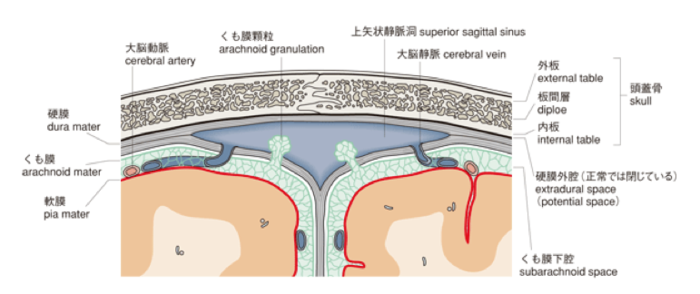

くも膜下腔内化学療法は、脳脊髄液 (CSF) を標的とする癌治療の一種です。 CSFは、主に脳の心室によって生成される無色の液体です。脳と脊髄を取り囲んで損傷から保護します。

これは、中枢神経系の周りに血液脳関門と呼ばれる保護層があるためです。この障壁により、毒素やその他の有害物質の侵入を防ぎながら、必要な栄養素と酸素が脳に入ることができます。

残念なことに、血液脳関門は、経口投与または点滴による抗がん剤の多くをブロックし、その効果を低下させる可能性もあります。

医師は、より標的を絞った化学療法を中枢神経系に施すために、くも膜下腔内化学療法を選択する場合があります。